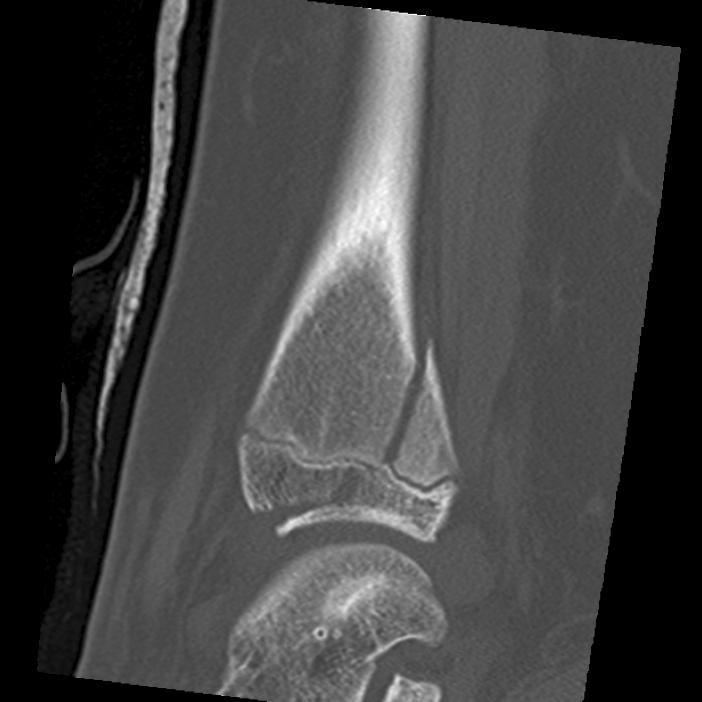

Xray

Type III / Tillaux on AP

Type II on lateral

CT

Type III on coronal

Type II on sagittal

3 point star on axial

Triplanar Fracture

Definition

- fracture in coronal, sagittal and transverse planes

- 2, 3 or 4 part

Varieties

2 part

- can be medial or lateral based of site of main distal fragment

- typically anterolateral epiphysis attached to posterior metaphysis

- anteromedial intact distal tibia

3 part

- additional separate anterolateral epiphysis / Tillaux